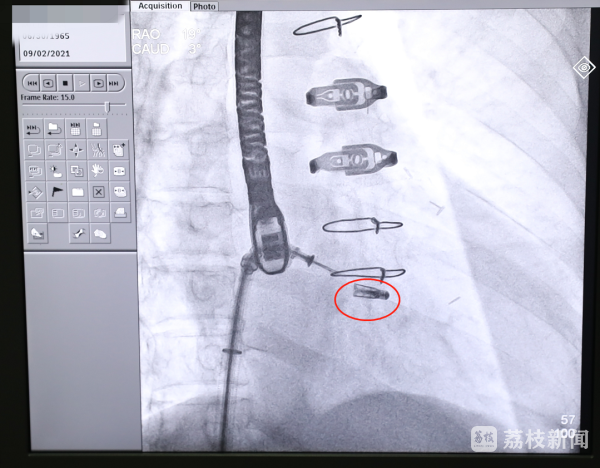

9月2日上午,在完成充分的术前准备和预案工作后,中大医院心血管内科、麻醉科、胸心外科等组成联合保障团队。在麻醉科医生成功实施全麻后,心血管内科马根山主任医师、丁建东主任医师、陈立娟主任医师、徐荣丰主治医师等开始施行介入手术,在食道超声和医学影像设备的引导下,手术专家经皮穿刺,借助先进的微创导管输送系统,通过逐级扩张鞘将可操控导引导管送入左心房,引导二尖瓣夹导管输送系统进入左心房;接着在左心房调整二尖瓣夹的位置。由于该患者病变复杂,二尖瓣夹闭的难度很大,相当于患者的二尖瓣上有个大口子,需要用一个夹子把二尖瓣的前瓣和后瓣夹起来,达到减轻反流的目。介入专家团队在手术过程中反复调整、多次探讨,最终成功夹合前后瓣的部分瓣叶,使之贴合在一起。经超声及医学影像造影检查证实,二尖瓣夹已夹紧,患者反流症状明显减轻,最终释放夹子,撤回输送系统,完成修复手术。术后,张先生的症状显著改善,目前,正在接受进一步观察治疗。